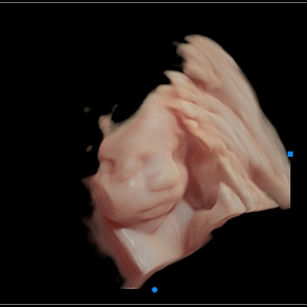

Weight: ~2.75 pounds (1.25 kg), the size of a Butternut Squash!

Length: ~15.2 inches (38.5 cm)

Development Highlights:

Brain continues rapid growth; folds are increasing.

Eyes can open and respond to light.

Fat continues to accumulate, smoothing out wrinkled skin.